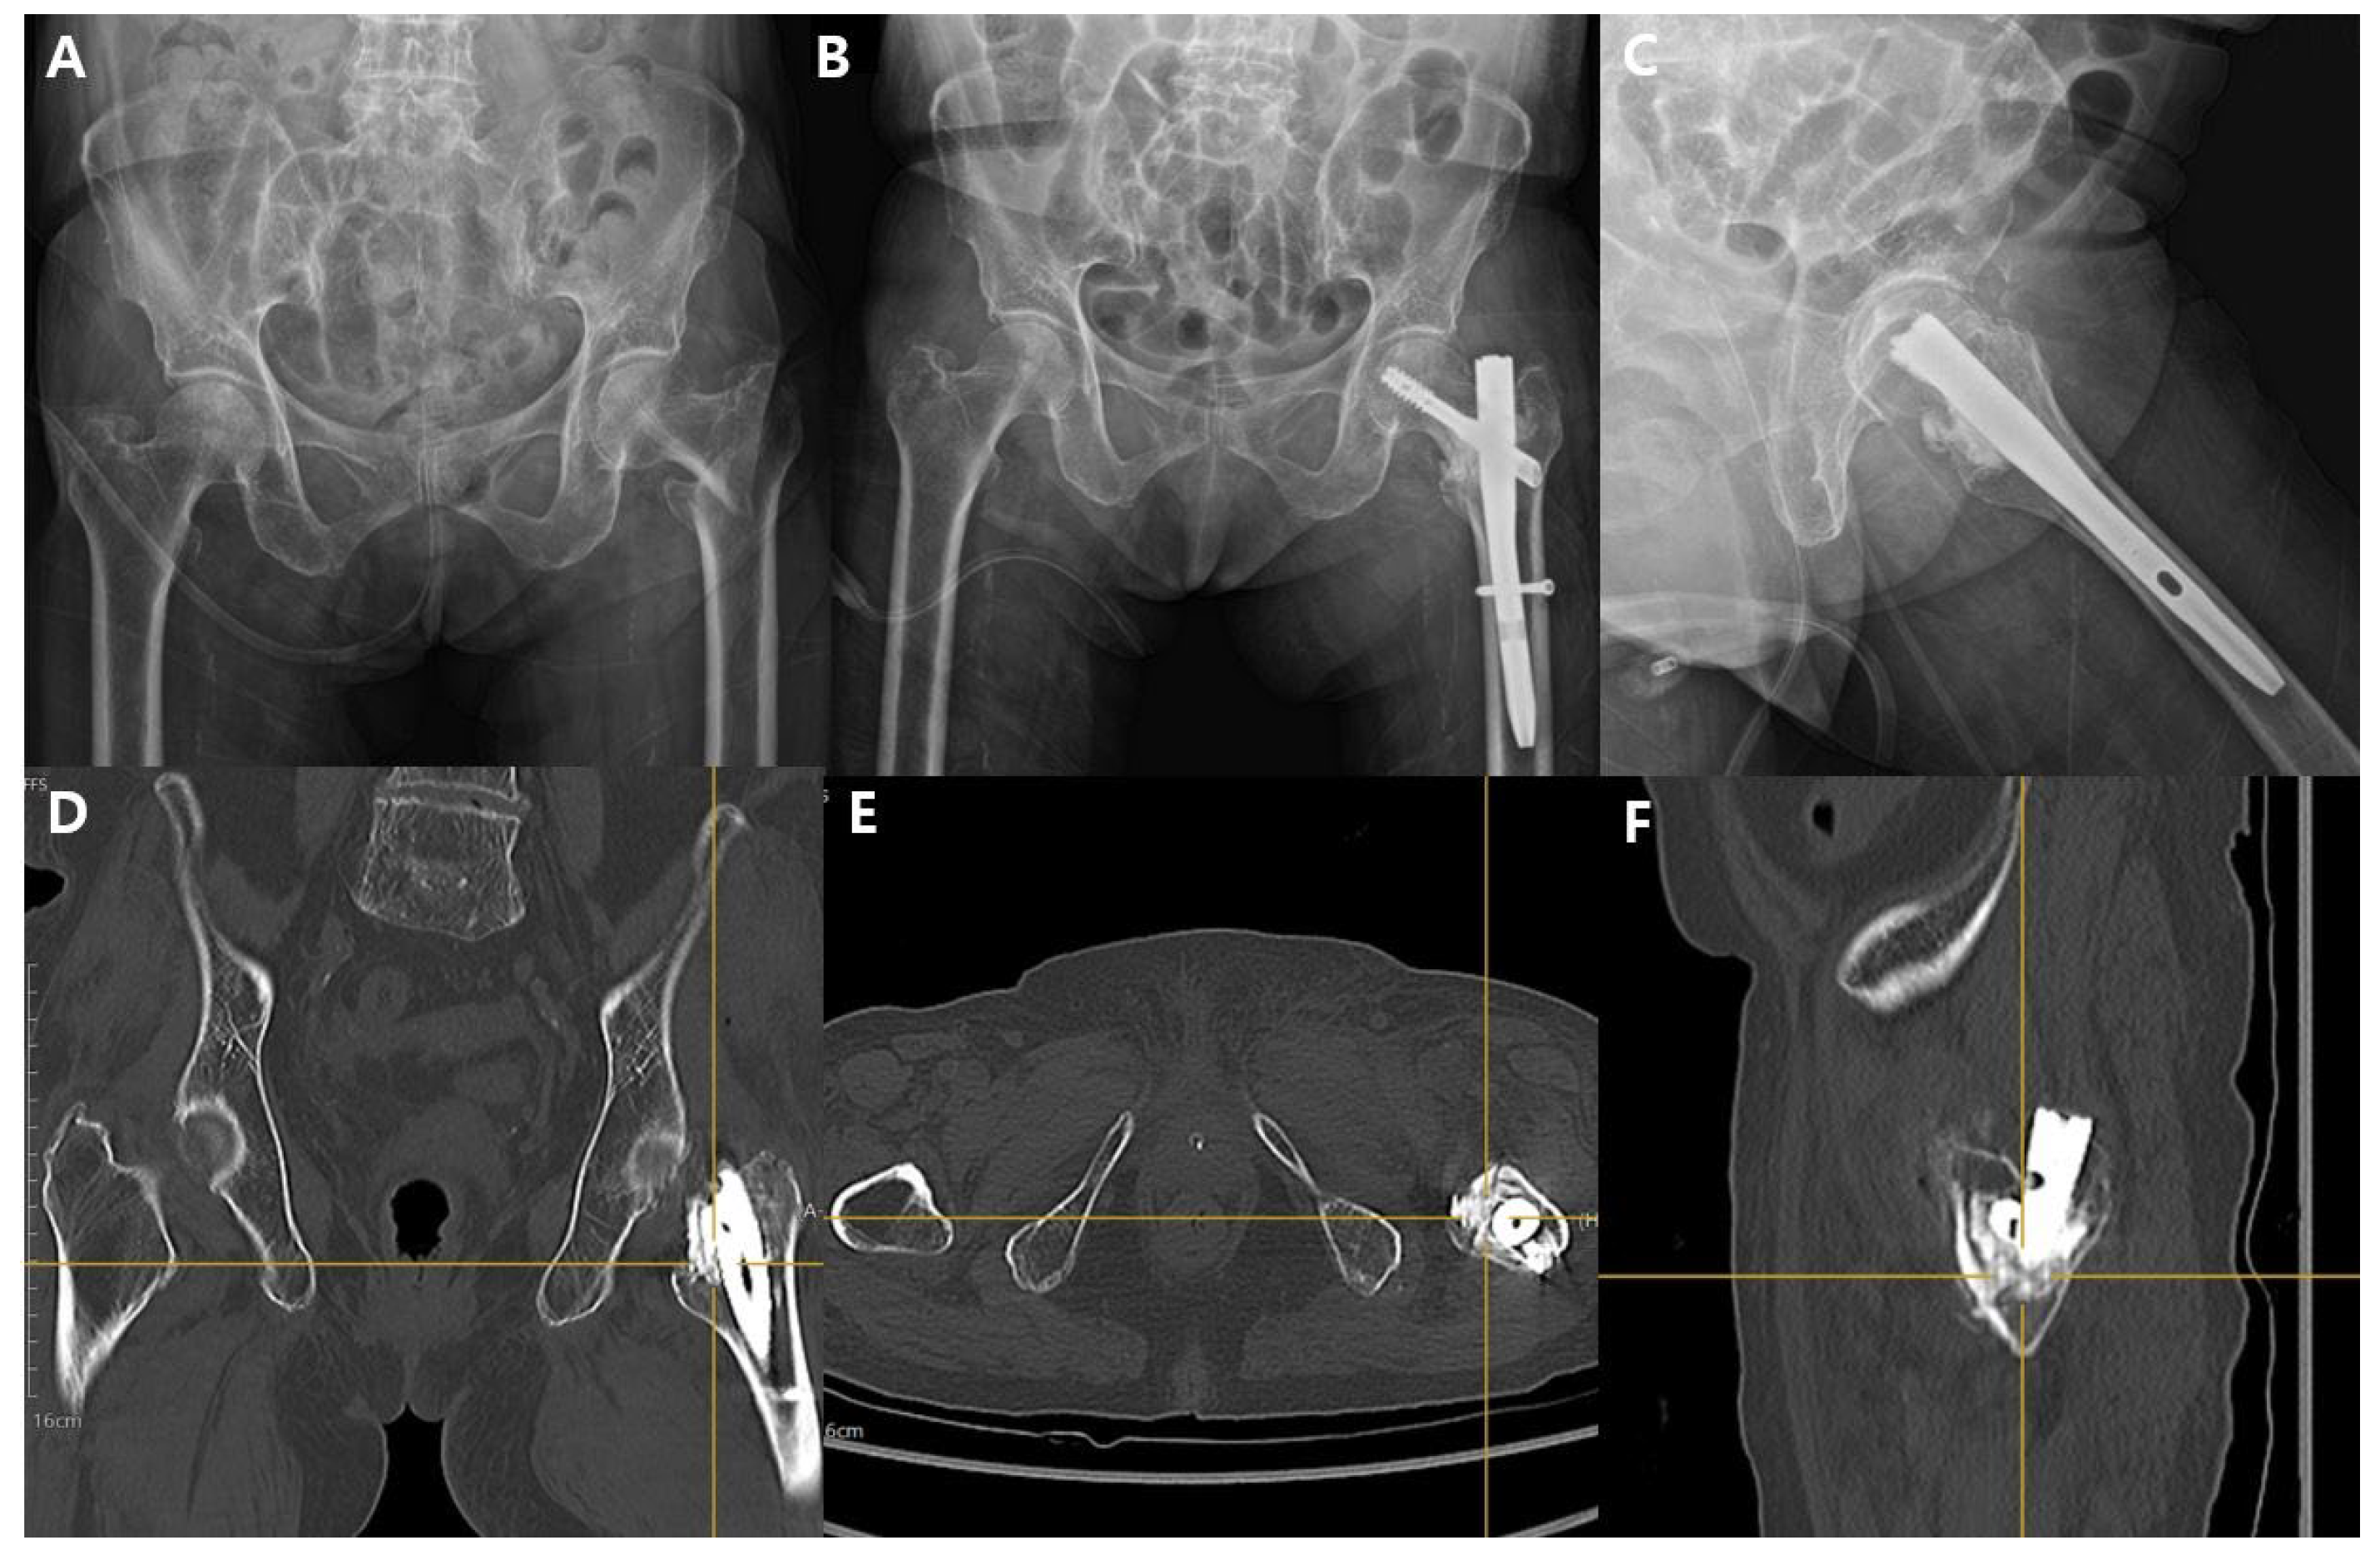

2.1. Surgical Technique